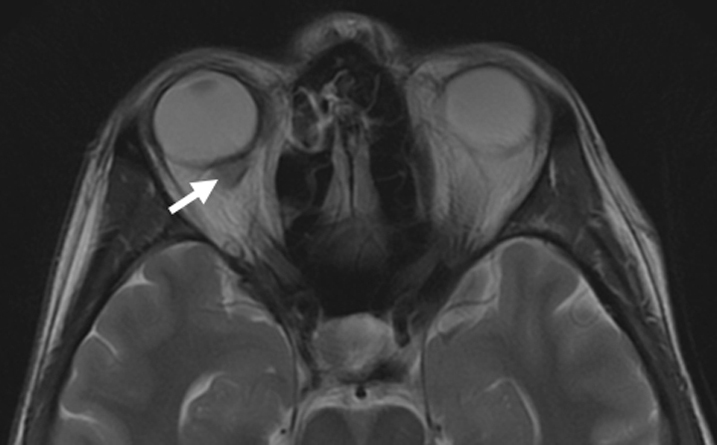

Clostridium septicum endophalmitis associated with colon adenocarcinoma

Jacob L. Eisenrich, BS, Angela M. Herro, MD, Mason Schmutz, MD, Kundandeep S. Nagi, MD